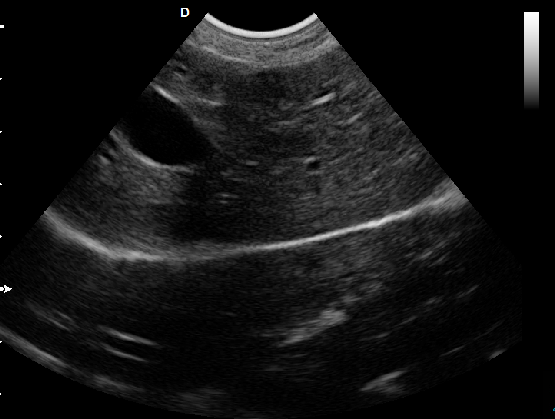

P5-VET便攜獸用彩超機頸動脈檢查圖

頸動脈血流:

頸動脈彩超是診斷、評估頸動脈壁病變的有效手段之一,在動脈粥樣硬化的流行病學調查和對動脈粥樣硬化預防、治療試驗的有效性評價中起著關鍵作用。

頸動脈彩超不僅能清晰顯示血管內中膜是否增厚、有無斑塊形成、斑塊形成的部位、大小、是否有血管狹窄及狹窄程度、有無閉塞等詳細情況, 并能進行準確的測量及定位,還能對檢測動脈的血流動力學結果進行分析。